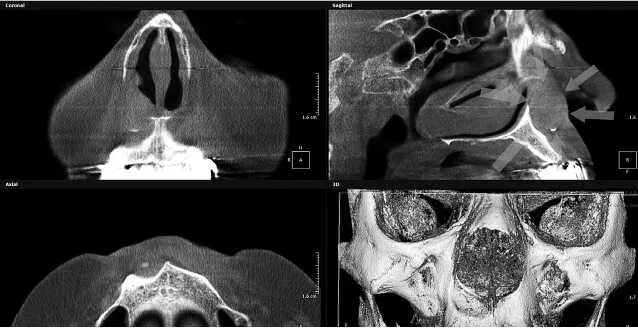

Как лечить утолщение слизистой верхнечелюстной пазухи